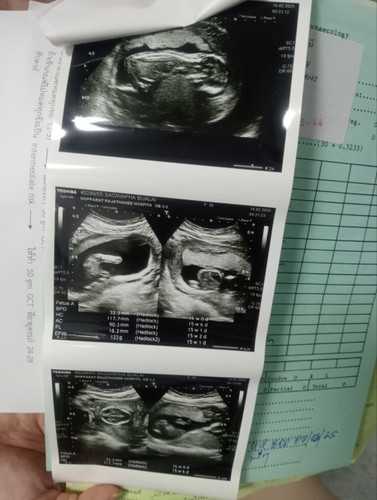

อยากถามแม่ๆว่าในรูปอัลตร้าซาวนด์15 Week รูปด้านบนสุดคือน้องนอนคว่ำใช่มั้ยค่ะขอบคุณสำหรับคำตอบนะค่ะ